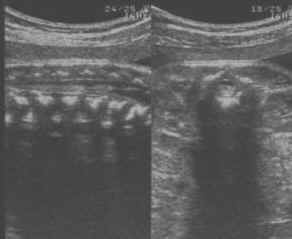

- Modifications sous tentorielles :

- Grande citerne inexistante,

- Vermis inférieur ectopique,

- Hémisphères cérébelleux attirés vers le bas formant une incurvation à concavité antérieure se moulant sur le tronc cérébral.

cliché droit

- V4 aplati, étiré,

- Horizontalisation de la tente du cervelet sur une coupe frontale postérieure céphalo-caudale.

- Modifications sus tentorielles :

- Feston frontal : Applatissement et rétrécissement bitemporal,

- Hydrocéphalie,

- Agénésie partielle du corps calleux fréquente,

- Troubles de la migration.